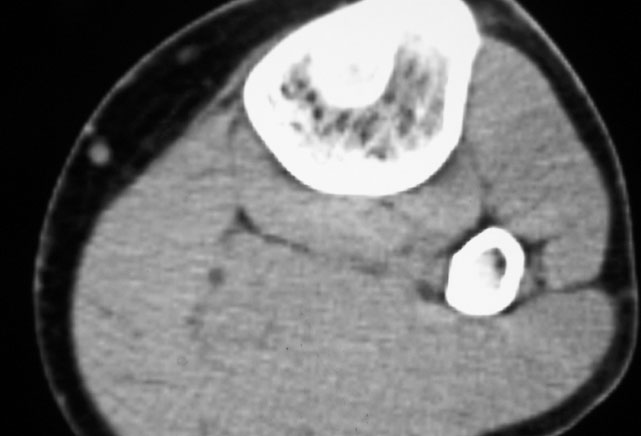

标题: CT19885:左胫骨上端肿瘤。 [打印本页]

标题: CT19885:左胫骨上端肿瘤。

男,20岁,医学院学生,11年前感左胫骨上端劳累后酸痛,曾由父母带到国内好几家有名望的医院诊治,但众说不一,所以基本上没有治疗。今年三月又开始出现症状,又到多家省级医院求治,但专家们的意见还是不能统一。各生化检查正常。mri考虑到胫骨上端良性血管瘤可能性大。ct考虑纤维瘤可能性大。请各位发表高见。